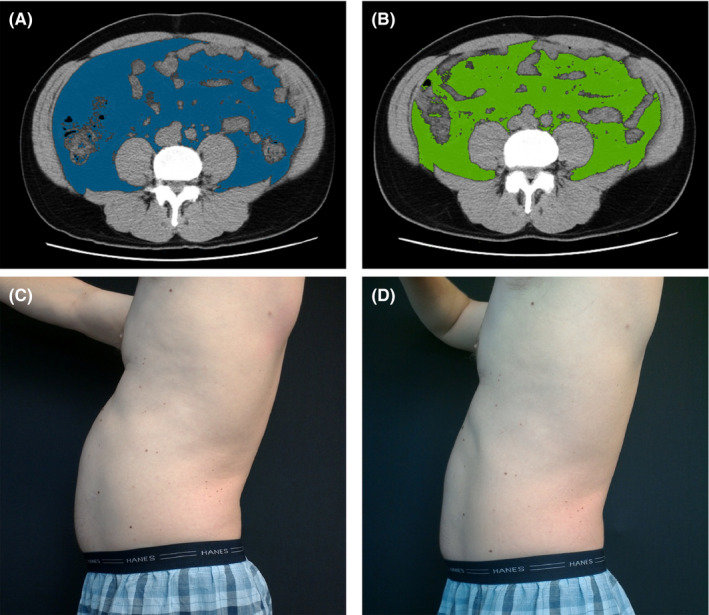

Too much of any body fat is bad for your health. But compared to the fat that lies just underneath your skin (subcutaneous fat), the visceral kind is more likely to raise your risk for serious medical issues. Heart disease, Alzheimer’s, type 2 diabetes, stroke, and high cholesterol are some of the conditions that are strongly linked to too much fat in your trunk.

Visceral fat is fat that wraps around your organs deep inside your body. You can’t always feel it or see it. In fact, you may have a pretty flat tummy and still have visceral fat. That’s sometimes called TOFI, or "thin outside fat inside." Only an expensive scan can measure how much belly fat is hiding in you, but your doctor won’t order a test just for that reason